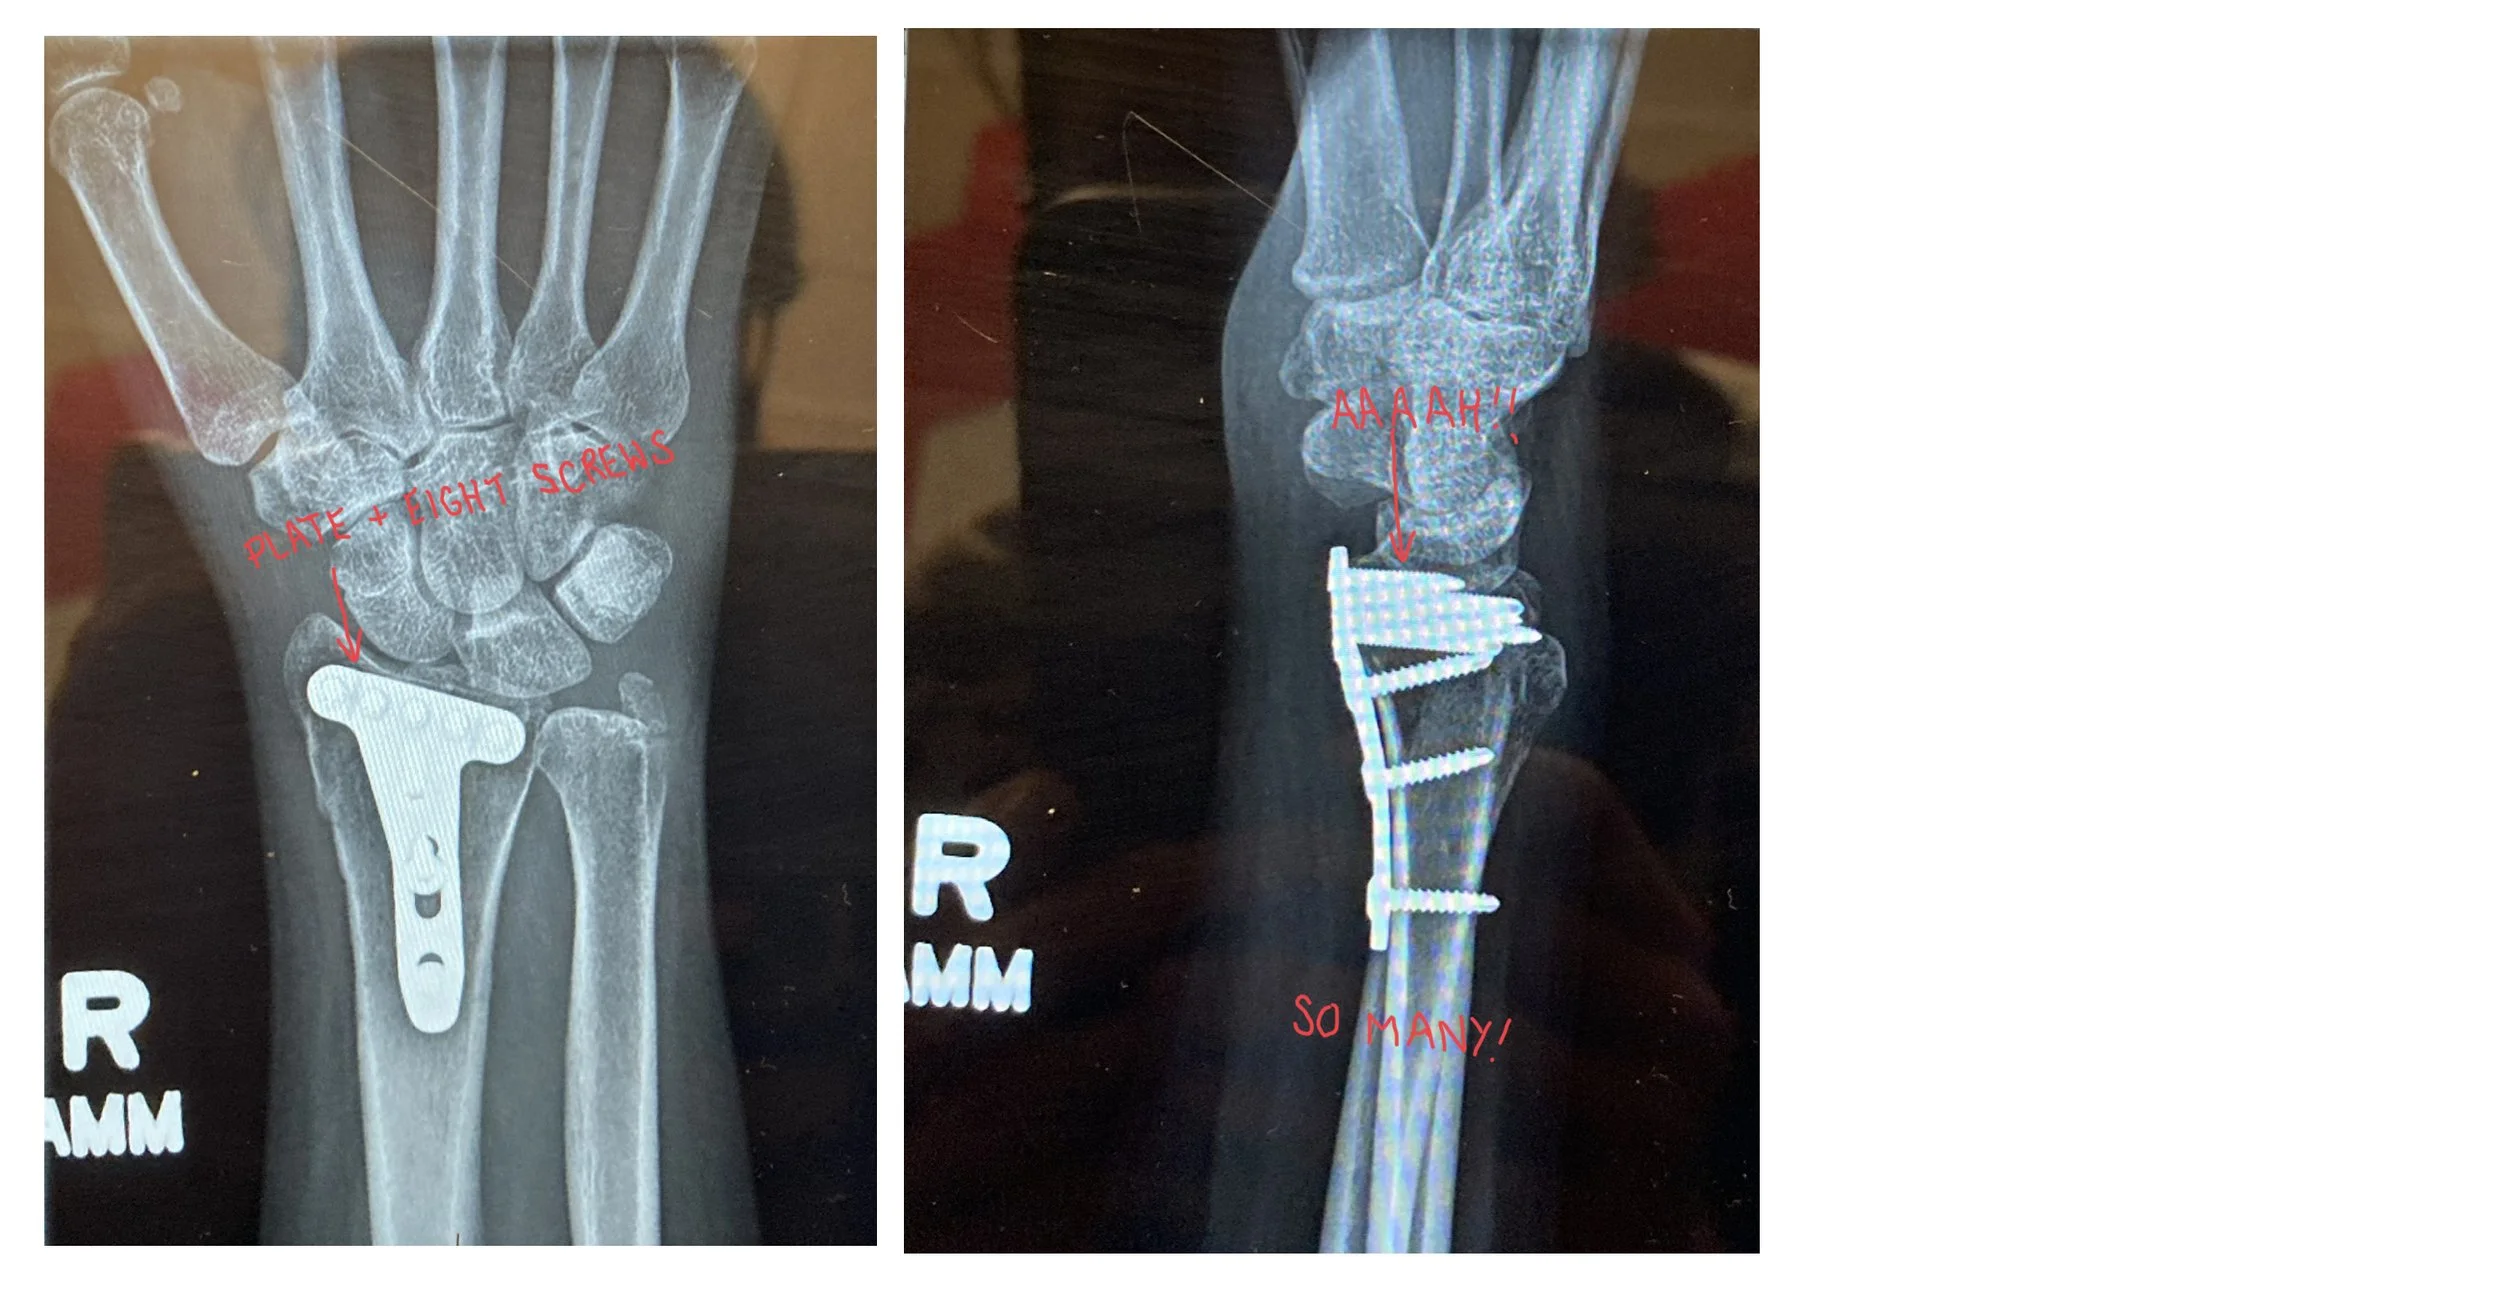

(Apologies for the reflections and satiations — the official copies didn’t arrive in time, so these were photographed from another screen because the program they were being viewed in blocks screen shots.)

As it turned out I was a candidate for surgery, which I was advised to have due to the severity of the break and the vagrant bone fragment; that happened on January 1st — two weeks after the original break. Everything was put back in its proper place, and a metal plate and eight screws which will remain in place indefinitely were installed.